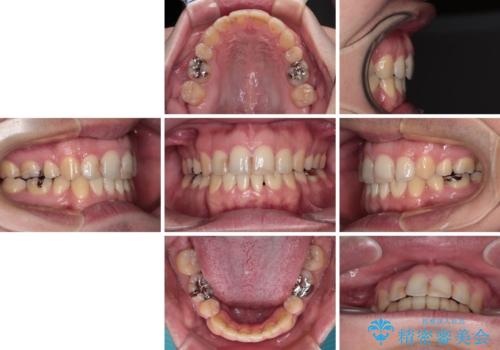

舌突出癖の改善トレーニングは、仕上がり、治療期間、そして治療後の後戻りに大きな影響を及ぼします。

トレーニングをしっかりと行っていただいたため、スッキリとした口元に仕上がりました。